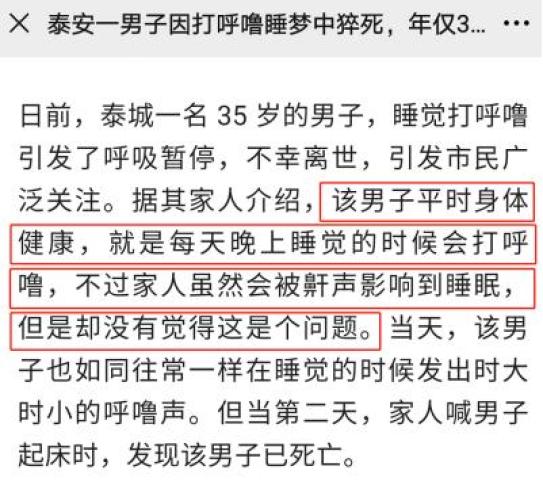

泰安一名35岁男子,在睡觉中呼吸暂停,不幸离世。他家人说,他平时身体健康,看不出任何问题。